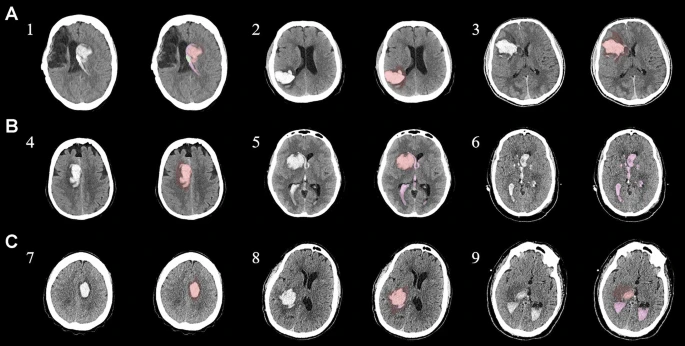

為了描述目的,患者按入組順序被賦予編號,并被連續(xù)分配到三組中的一組,每組三名。根據(jù)模型2分割,ICH體積范圍為0.1至54.9mL(平均ICH體積為23.5mL)。5名ICH患者受累于局限性腦葉,其余患者受累于基底神經(jīng)節(jié)或外囊深處。3名患者的ICH位于丘腦(圖1),1名患者的血腫位于多個腦結(jié)構(gòu)(即尾狀核、殼核和蒼白球)。平均而言,MSCs是在ICH后3天注射的。